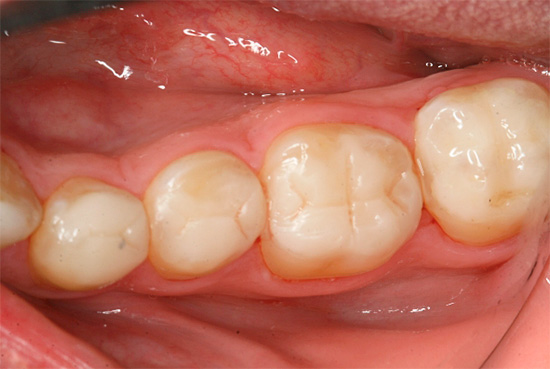

Ed è così che appare il trattamento della carie profonda al microscopio, tutti gli stadi sono ben tracciati